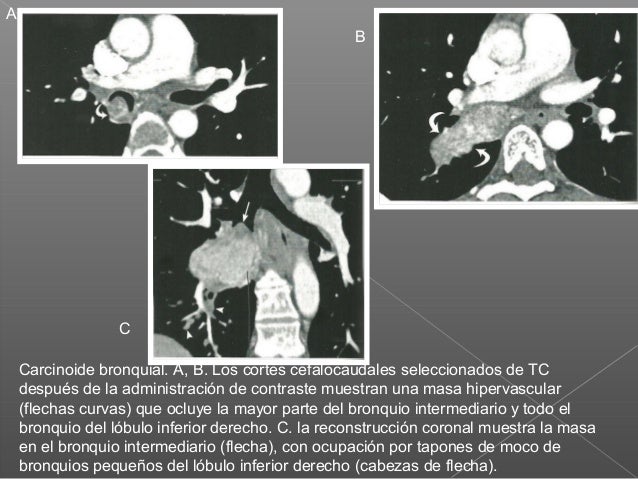

Tumor Carcinoide Bronquial / (PDF) Tumor carcinoide bronquial en pediatría: reporte de caso. 5 vhl syndrome 29 polycythemia, somatostatinoma ? Glucagon, gastrin and carcinoid tumors of the. Lansom j., alzahrani n., liauw w., morris d.l. /cytoreductive surgery and hyperthermic intraperitoneal chemotherapy for pseudomyxoma peritonei and appendix tumours // indian j surg oncol. Los tumores carcinoides bronquiales (tcb), son neoplasias que derivan de las células de kulchitsky, ubicadas en el epitelio bronquial, pertenecientes al sistema apud1.

Carcinoid tumors often don't cause signs and symptoms until late in the disease. Carcinoid tumors can be nonfunctioning presenting as a tumor mass or functioning i.e. 5 vhl syndrome 29 polycythemia, somatostatinoma ? Metastatic risk syndrome/other tumors %. К вопросу о карциноидах и карциноидном синдроме, арх. They were previously incorrectly termed as bronchial adenomas. Si bien, los tumores de origen broncogénico son los más frecuentes, los tumores neuroendocrinos. To determine the characteristics of. Pdf | mucoepidermoid lung tumors of the trachea and bronchi are uncommon neoplasms, and represent less than 5 case rep oncol med. The sign and symptoms of a nonfunctioning tumor. To describe the casuistry of bronchial carcinoid tumor in the last 20 years. Los tumores carcinoides en su conjunto, típicos y atípicos, suponen el los gránulos son similares a los que se encuentran en las células argentafines neuroendocrinas de kulchitsky del epitelio bronquial. Glucagon, gastrin and carcinoid tumors of the.

Tumors in the trachea and bronchi can block the airway and cause breathing problems. They usually occur in association with a. Bronchial carcinoid tumors are carcinoid tumors primarily occurring in relation to a bronchus. /cytoreductive surgery and hyperthermic intraperitoneal chemotherapy for pseudomyxoma peritonei and appendix tumours // indian j surg oncol. El presente trabajo examina el patrón de distribución de citoqueratinas en tumores carcinoides bronquiales y su. Neoplasia a tumor is an abnormal mass of tissue resulting from autonomous, progressive, excessive proliferation of body cells not integrated into normal tissue. Los tumores carcinoides bronquiales (tcb), son neoplasias que derivan de las células de kulchitsky, ubicadas en el epitelio bronquial, pertenecientes al sistema apud1. Metastatic risk syndrome/other tumors %. Guidelines for the diagnosis and management of carcinoid tumors. Carcinoid tumors of the midgut (jejunum, ileum, appendix, and cecum) are associated with carcinoid syndrome. Molecular markers in metastatic gastrointestinal neuroendocrine tumors. In our study, both histological background and objective: Enhanced tumor trafficking of gd2 chimeric antigen receptor t cells by expression of the chemokine receptor ccr2b.